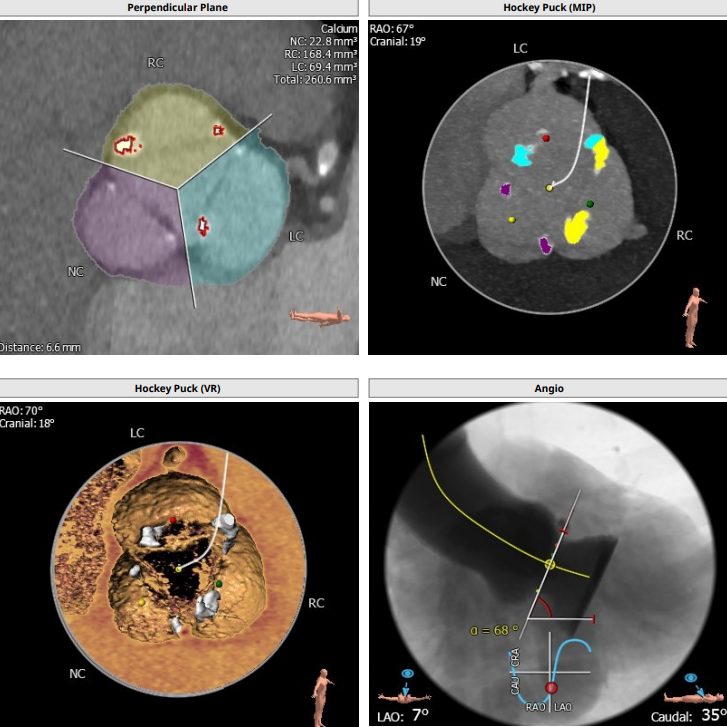

患者男,83岁,解剖为三叶瓣,瓣环径25.5,LVOT25,法式窦结构大,长短颈均超过43,左冠高度16.2,右冠高度18.4,STJ39.9,高度为27.7,升主动脉稍增宽,均径在40.1。

综合整体结构,决定选用VenusA29号瓣膜进行植入,VenusA29号瓣膜29MM的瓣环经相对于25.5的瓣环解剖,25的LVOT有13%以上的oversize,且STJ高度为39.9,升主为40.1,相对于VenusA29号瓣膜最大处44的特点,均可以提供锚定力。

根部解剖: